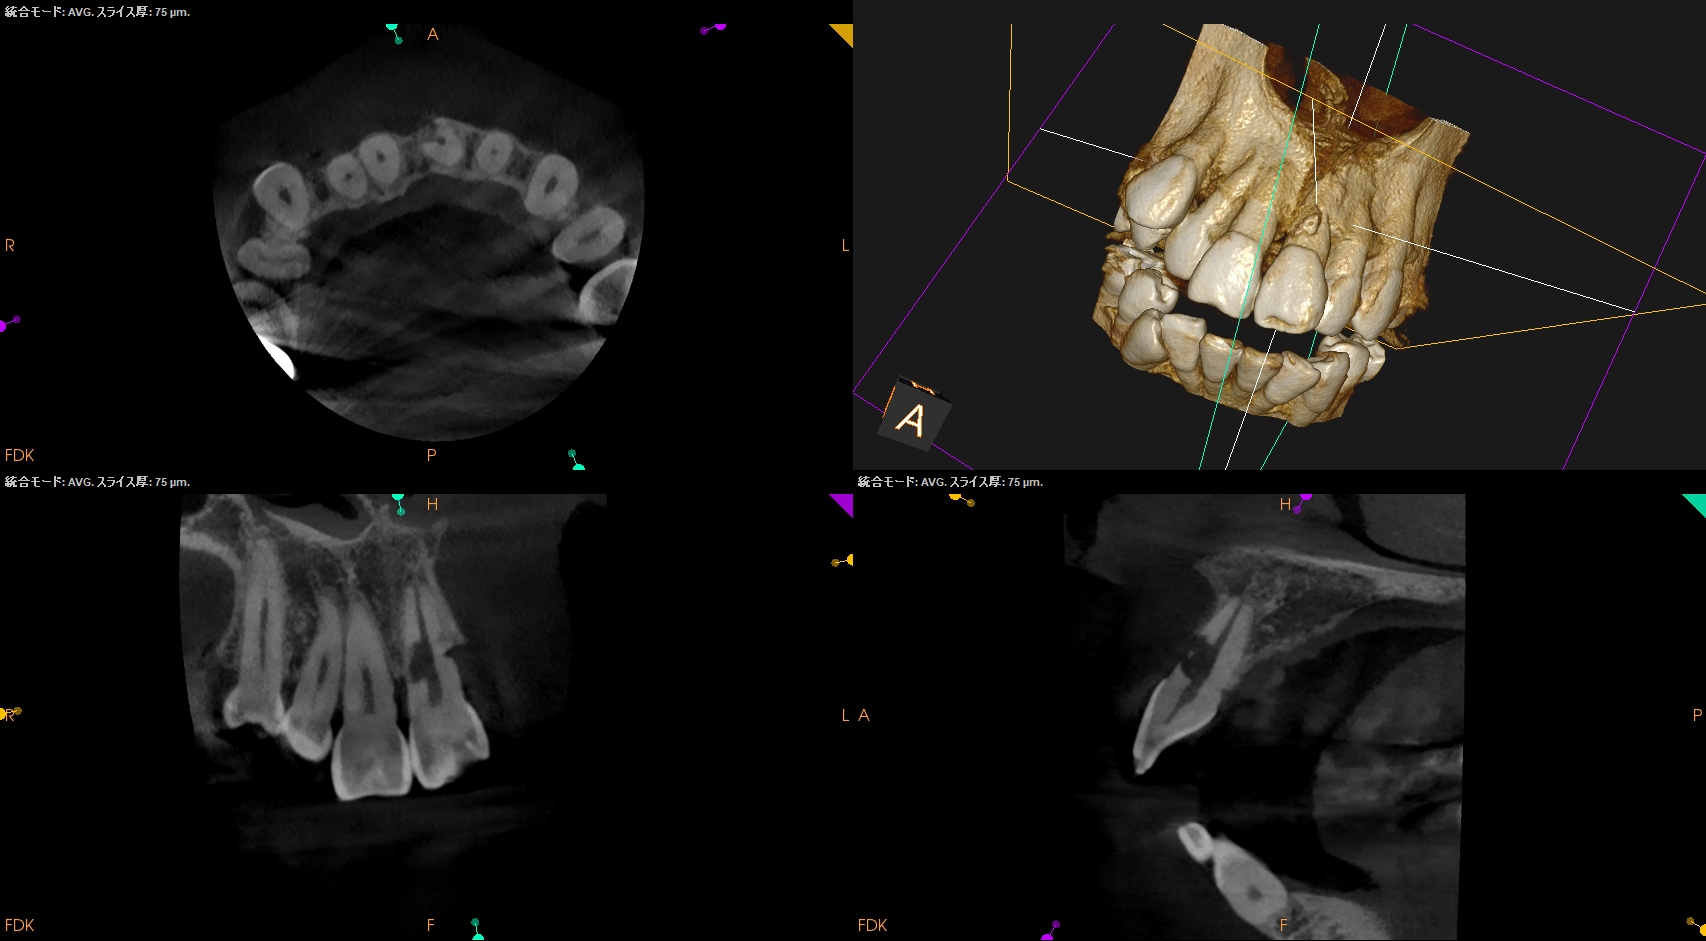

Pre-op Endo Test(2026.1.28)

#9の頬側に大きな穴がある。が、根尖病変はない。

根完成永久歯の再植後に、歯髄のRevascularizationは起きないことから本来は根管治療が必要だが、それがなされていないことからこの病態が発生したのかもあしれない。

根管治療して、支台築造して、外部吸収のRepairだが、

根管治療すると外部吸収部位が薄皮一枚で交通しているのがネック